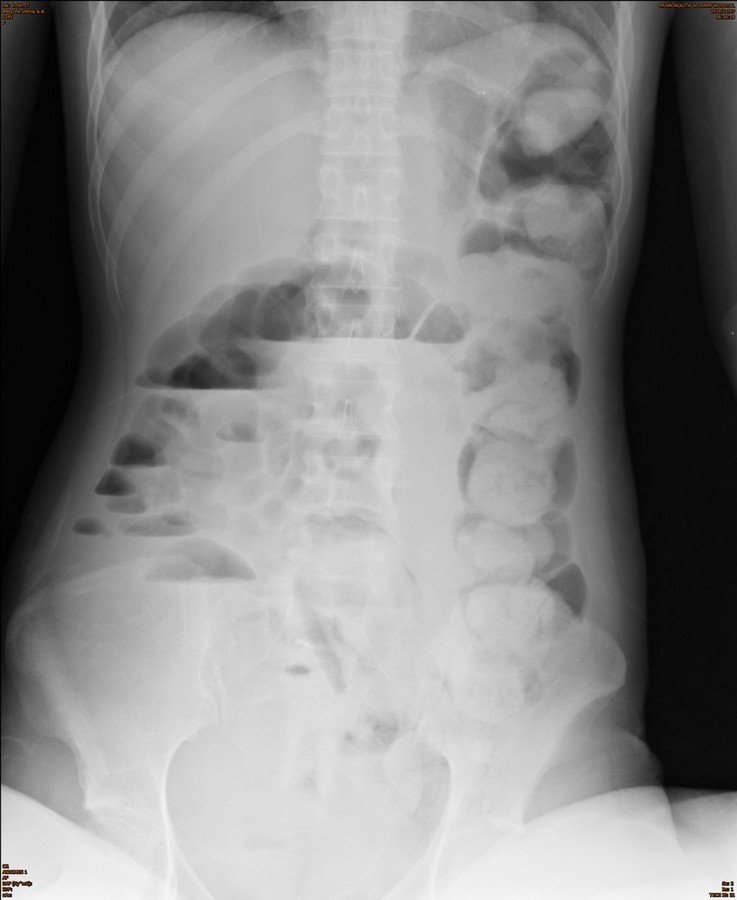

History : A 30-year-old female with weight loss and constipation

Which abnormality is not seen in this film?

A. Large bowel dilatation

B. Small bowel dilatation

C. Stomach dilatation

D. Fecal impact

Answer : C. Stomach dilatation is not seen in this film

Additional plain film abdomen : upright

Air fluid levels with different height in the same loop of in dilated large bowel and small bowel.

Radiological finding :

• Colonic dilatation and fecal impaction at left side colon to the level of sigmoid colon

• Abrupt change of the colonic lumen at rectum

• Associated small bowel dilatation

Answer 1 : Large bowel obstruction

Answer 2 : Partial obstruction, because can see air in the rectum

Answer 3 : Site of obstruction : Rectum